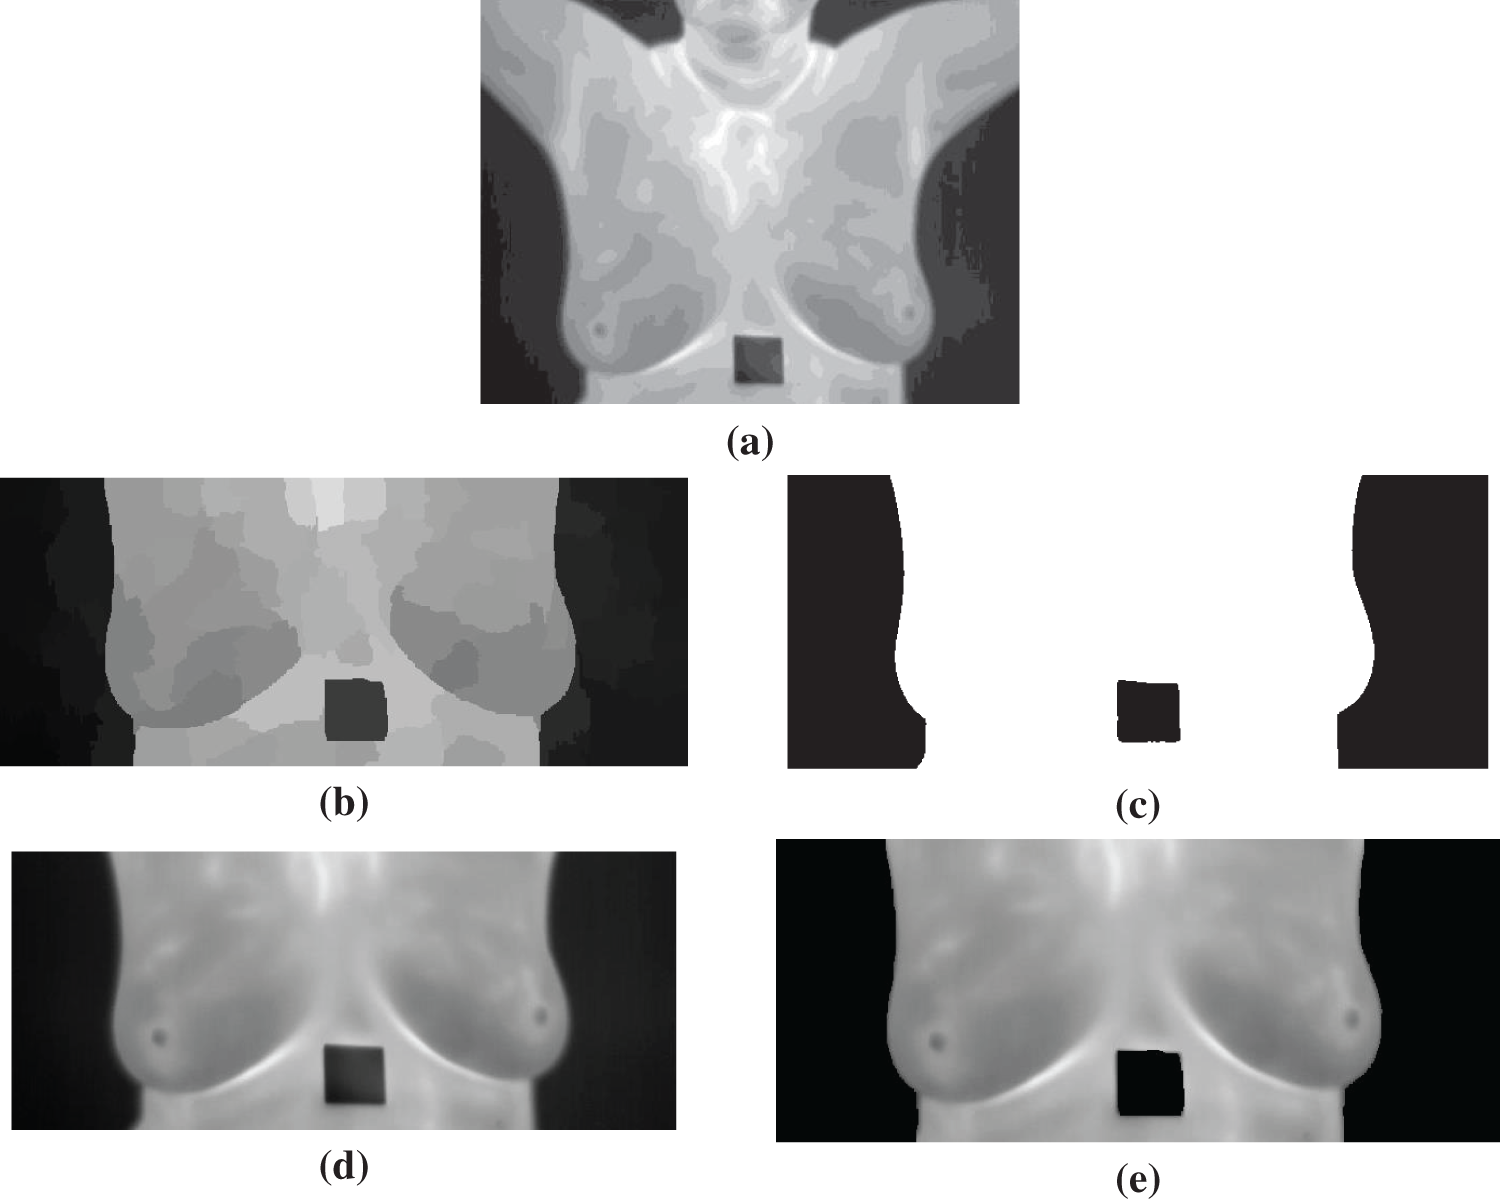

where R is a random number between 0 and 1, and

The conducted experiments are presented and discussed in this section. As the first step after preprocessing the dataset is to segment the regions of interest to be considered for further processing, Fig. 4 shows the results of the segmentation process. As shown in the figure, the output of each step in the segmentation process is presented in the figure. Although the result is shown in Fig. 4d, we applied image filtering to get more enhanced images to achieve accurate classification results; thus, the final result of the image segmentation process is shown in Fig. 4e. This image is fed to the feature extraction and feature selection to select the most significant features for further processing and classification.

Figure 4: Segmentation results for the thermal image from the dataset (a) Original image, (b) Quick-Shift superpixels, (c) Otsu’ thresholding result, (d) Final segmented image, (e) Filtered final image